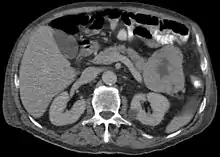

ACC are typically large, up to 10 cm, and soft compared to pancreatic adenocarcinoma, lacking its dense stroma. They can arise in any part of the pancreas.[2]

Histomorphologically, the tumour resembles the cells of the pancreatic acini and, typically, have moderate granular cytoplasm that stain with both PAS and PASD.[4]

Light microscopy of an acinar cell carcinoma biopsy typically shows granular appearance.[5] Immunohistochemistry is usually positive for trypsin, chymotrypsin and lipase.[5] On genetic testing, altered genes/proteins are typically found for p53, SMAD4, APC, ARID1A and GNAS.[5]